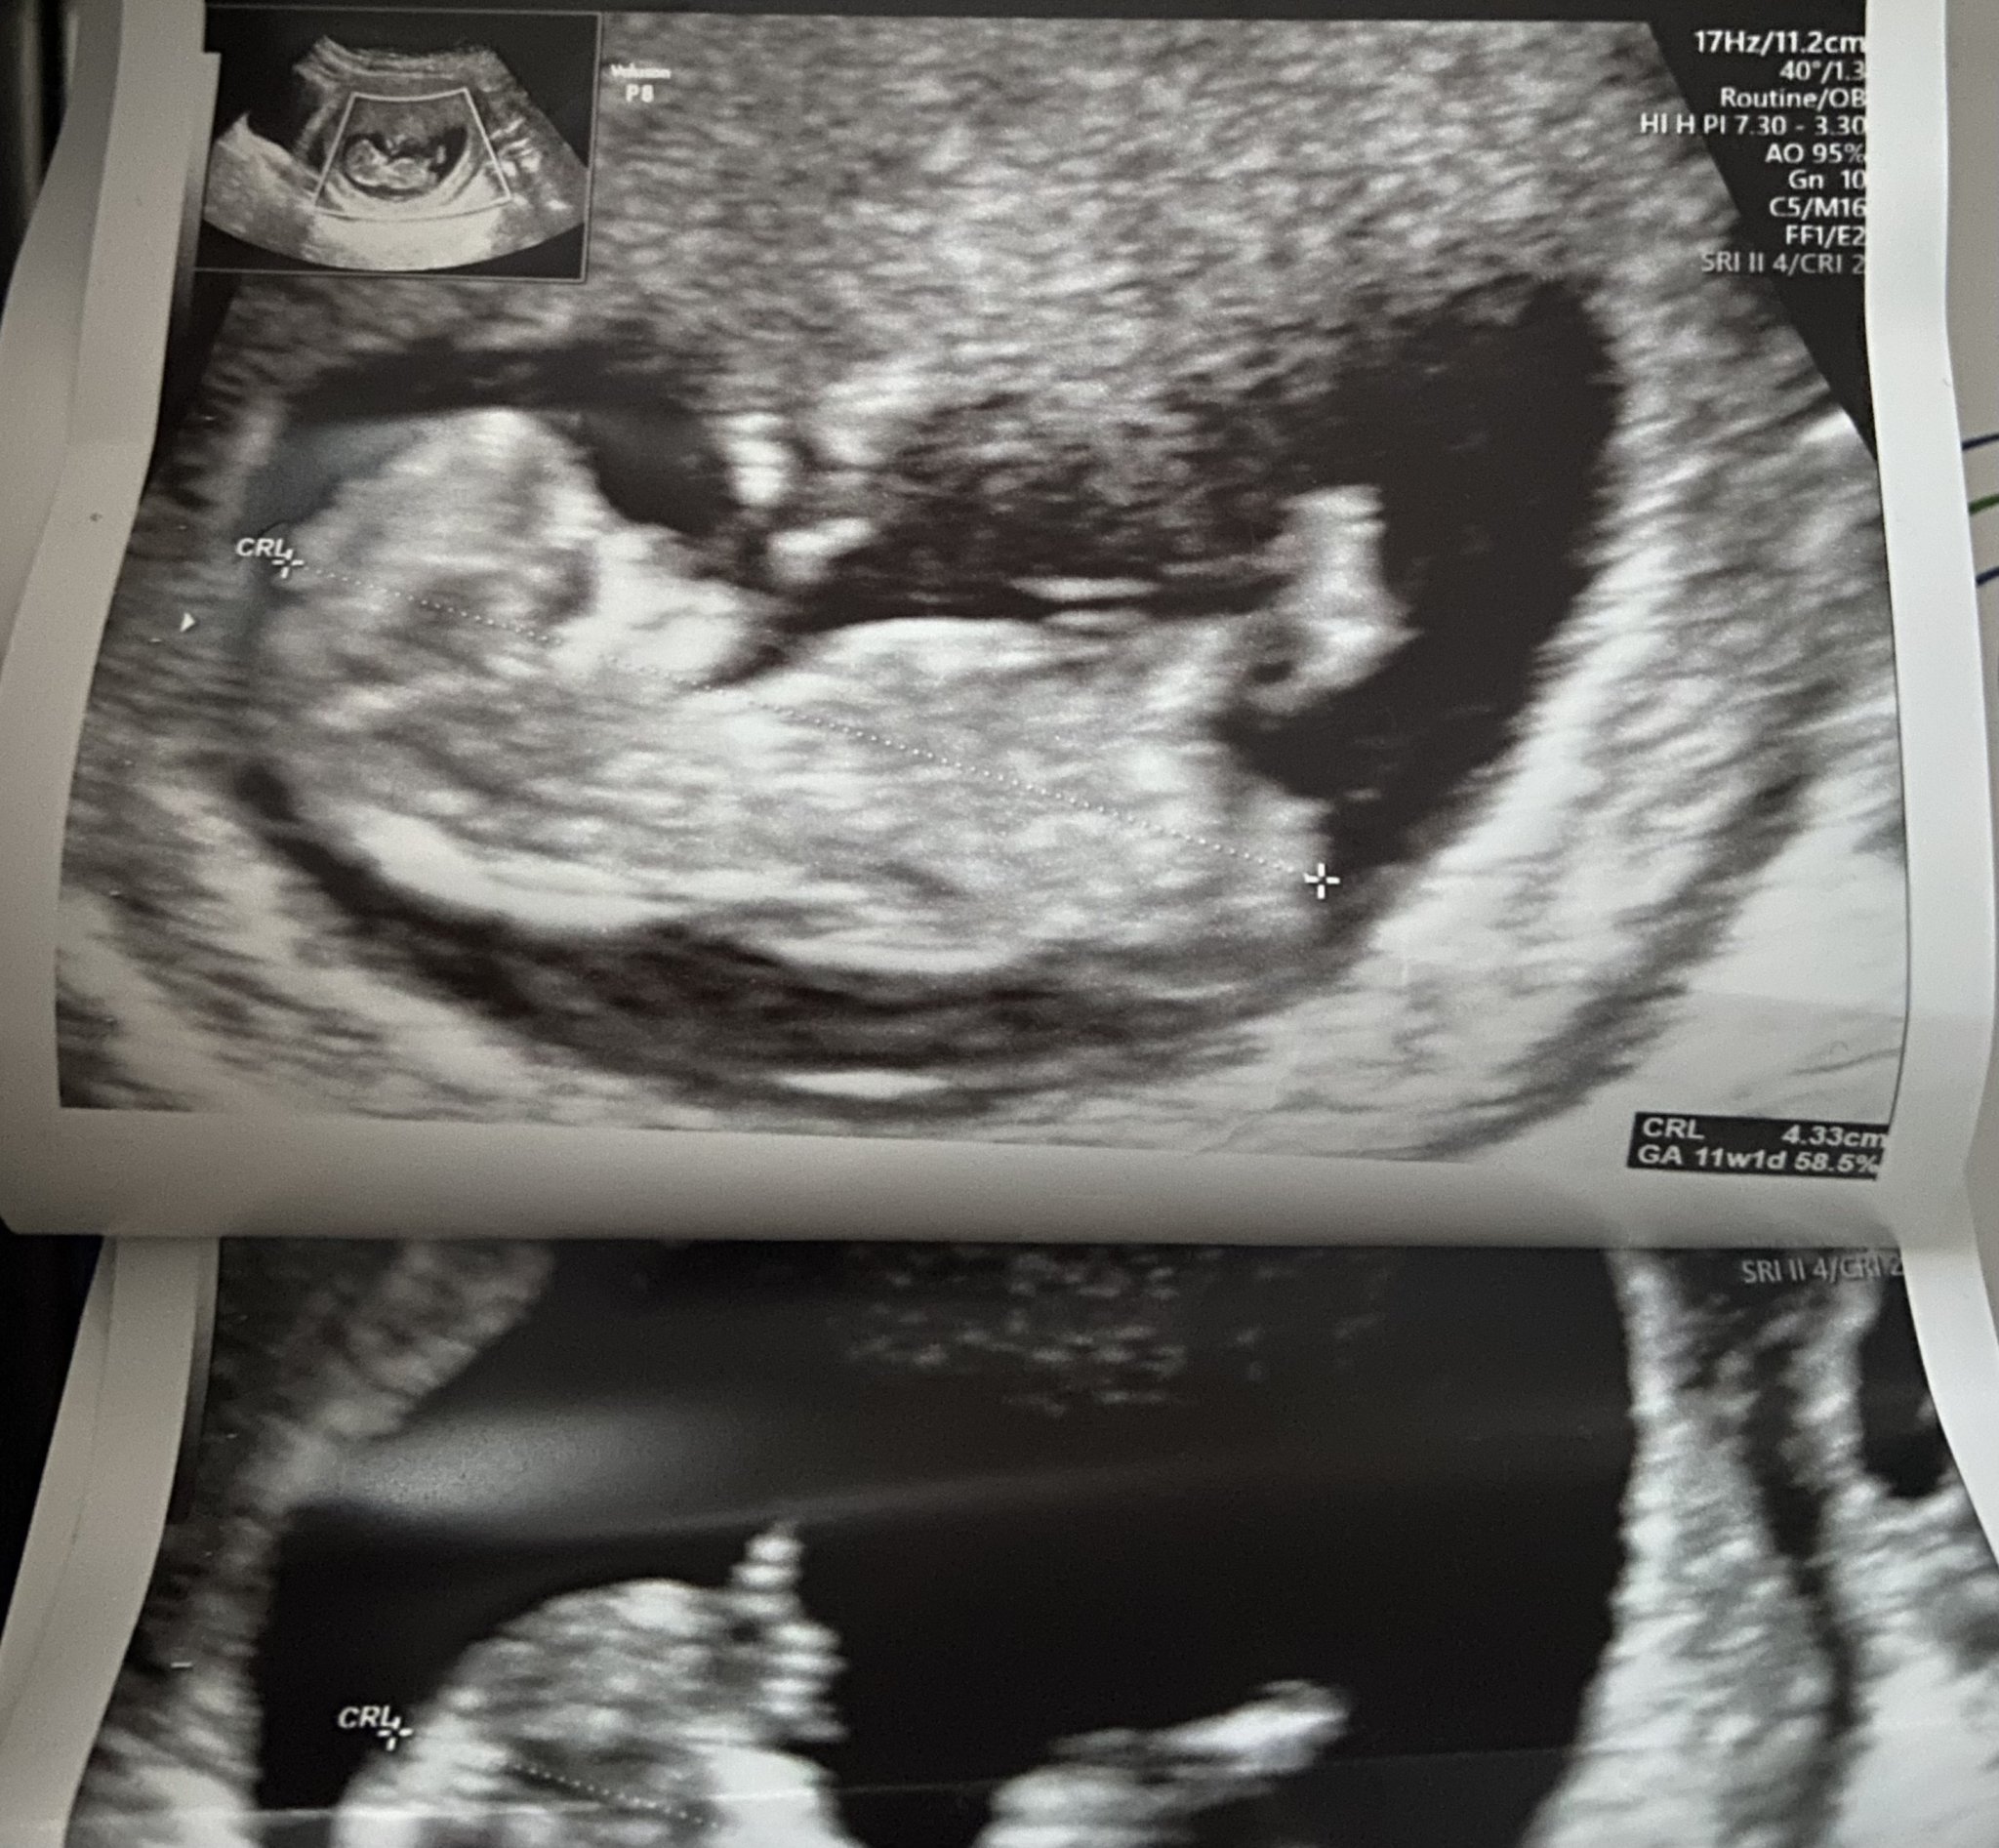

Какво представлява пренаталният тест и защо се провежда?